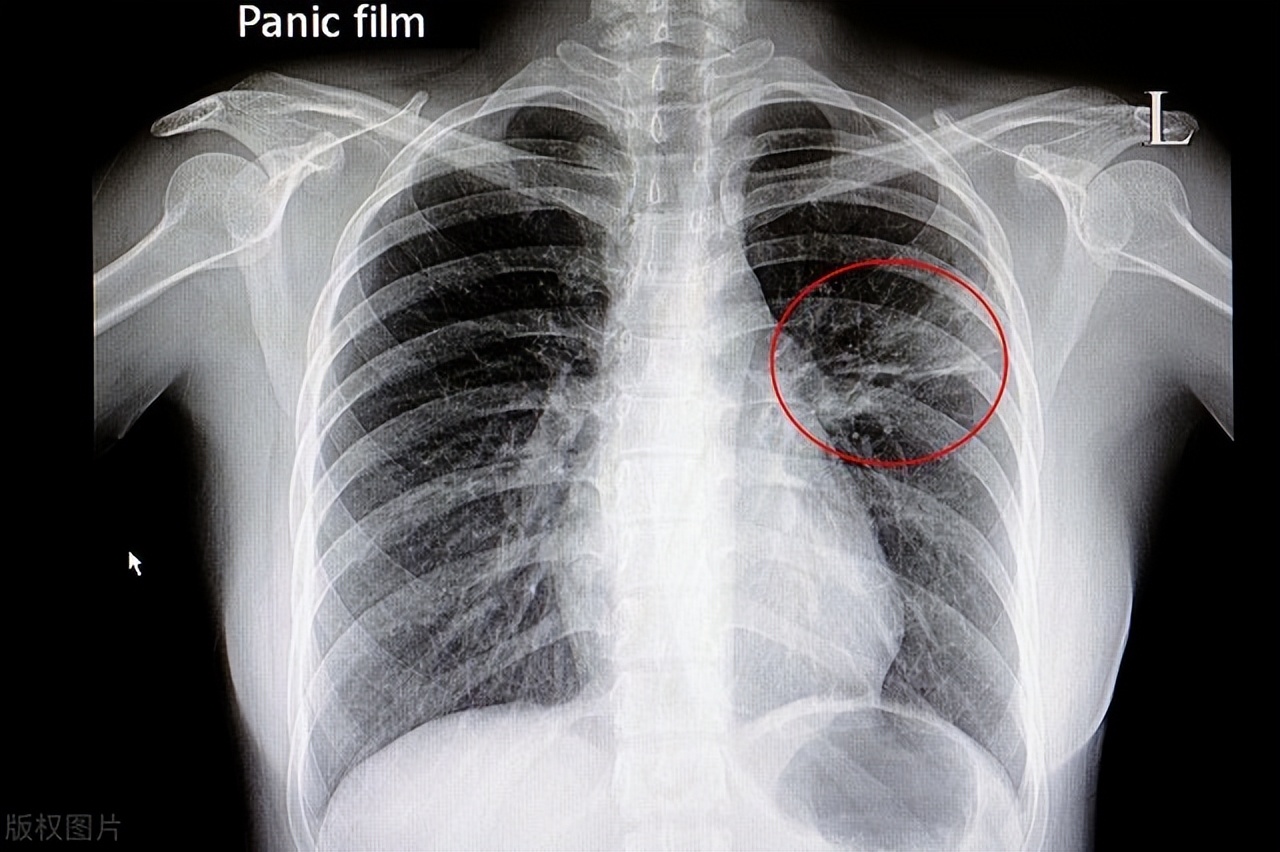

二、CT检查的重要性

CT(计算机断层扫描)检查是一种高精度的影像学检查技术,可以对肺部进行立体成像,检测出肺部的任何异常变化。在肺炎的诊断和治疗中,CT检查具有非常重要的作用。

以下是CT检查在肺炎中的重要性:

1.发现肺部病变: CT检查可以在很短的时间内生成高精度的三维图像,可以显示出肺部的任何异常变化。这有助于医生快速准确地发现肺部病变,尤其是早期肺炎病变。

2.确定肺炎类型: CT检查可以帮助医生确定肺炎的类型,例如细菌性肺炎、病毒性肺炎等。不同类型的肺炎需要不同的治疗方案,CT检查可以帮助医生制定出最佳的治疗方案。

3.观察病情进展: 在肺炎治疗过程中,CT检查可以帮助医生观察病情的进展情况。如果治疗不当或病情严重,肺部病变可能会继续扩散。CT检查可以帮助医生及时调整治疗方案,避免病情恶化。

4. 指导手术治疗: 在极少数情况下,肺炎可能需要手术治疗。CT检查可以帮助医生确定手术的范围和部位,提高手术治疗的精度和成功率。